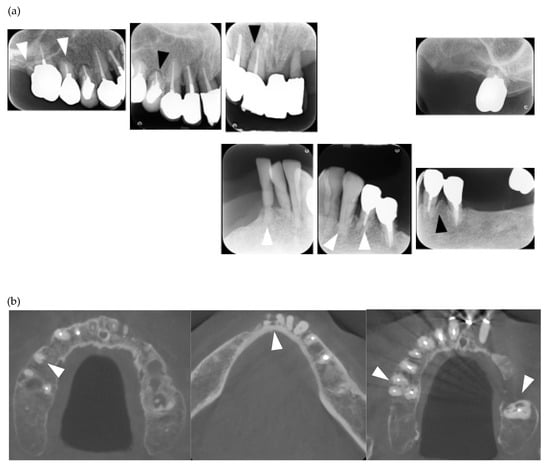

Figure 1.

Multiple external root resorption and calcinosis at the oral region in pt. 2. A dental X-ray photo and cone beam computed tomography (CBCT) image of teeth (a,b) and the deposition of calcinosis at the nasal spur (c). The white arrowhead indicates root resorption, black arrowhead shows periodontal ligament (PDL) space widening and the white arrow, calcinosis.

In the present study, MERR was detected in four SSc patients, including one described in a case report (pt. 1) [12]. The causes of external resorption, including trauma, periodontal and periapical inflammation, orthodontic treatment, internal bleaching or tumors, were not found in the teeth having external resorption. Dental X-rays and CBCT images showed that MERR was observed in six, six, and four teeth in pts. 2, 3, and 4, respectively (Figure 1a, Figure 2a and Figure 3a). A widening PDL space was detected in all patients. A space between canines and premolars in the upper jaw was found in pts. 3 and 4 (Figure 2a and Figure 3a). Furthermore, the deposition of calcinosis in the nasal spur was noted in pts. 1, [12], 2, and 3, while calcinosis in the palatal plate was observed in pt. 4 (Figure 2c and Figure 3c).